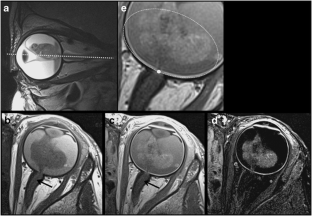

Assessment of early-stage optic nerve invasion in retinoblastoma using high-resolution 1.5 Tesla MRI with surface coils: a multicentre, prospective accuracy study with histopathological correlation

This IRB-approved, prospective multicenter study included 95 patients (55 boys, 40 girls; mean age, 29 months). 1.5-T MRI was performed using surface coils before enucleation, including spin-echo unenhanced and contrast-enhanced (CE) T1-weighted sequences (slice thickness, 2 mm; pixel size <0.3 × 0.3 mm2). Images were read by five neuroradiologists blinded to histopathologic findings. ROC curves were constructed with AUC assessment using a bootstrap method.

Histopathology identified 41 eyes without ON invasion and 25 with prelaminar, 18 with intralaminar and 12 with postlaminar invasion. All but one were postoperatively classified as stage I by the International Retinoblastoma Staging System. The accuracy of CE-T1 sequences in identifying ON invasion was limited (AUC = 0.64; 95 % CI, 0.55 – 0.72) and not confirmed for postlaminar invasion diagnosis (AUC = 0.64; 95 % CI, 0.47 – 0.82); high specificities (range, 0.64 – 1) and negative predictive values (range, 0.81 – 0.97) were confirmed.

HR-MRI with surface coils is recommended to appropriately select retinoblastoma patients eligible for primary enucleation without the risk of IRSS stage II but cannot substitute for pathology in differentiating the first degrees of ON invasion.

Fig. 5